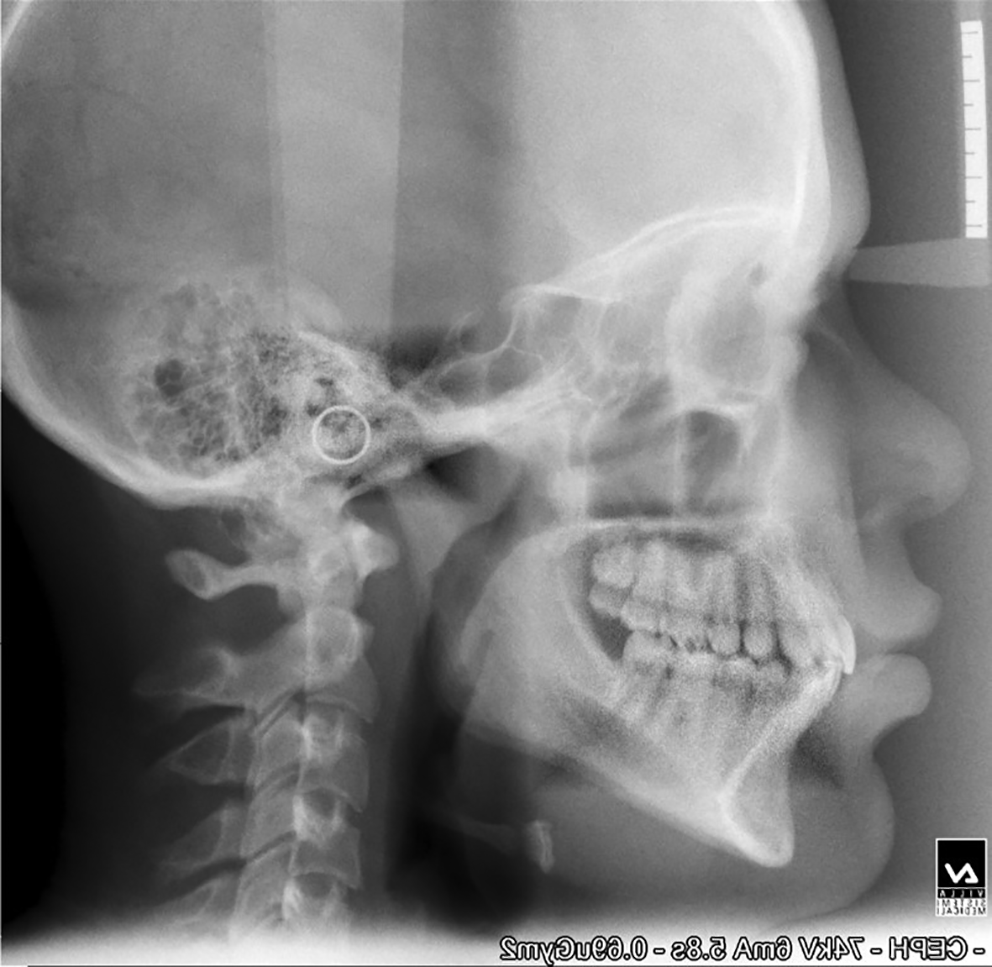

The mean age of the patients at the start of treatment was 12 years. Pre-and post-treatment lateral cephalograms were taken and evaluated for skeletal, dental, and soft tissue changes after wearing a twin block appliance therapy for nine months. Cephalometric changes during treatment are shown in Table 1. Figure 1 shows pre-treatment cephalograms, Figure 2 shows post-treatment cephalograms and Figure 3 shows the superimposition of pre-and post-treatment average digitizations. Twin block appliance wearing resulted in rapid skeletal correction as was evident from a statically significant decrease in angle Point A-Nasion-Point B (ANB), from 7.07±1.98 to 3.33±1.23 degrees (P=0.02); the angle of convexity decreased significantly from 9.87±1.5 to 5.13±1.24 degrees (P=0.01). There was a significant change in Wits appraisal, which decreased from 4.87±0.91 to 3.33±0.72 mm (P=0.04). Angle between Sella-Nasion-Point B (SNB) increased significantly from 74.0±1.46 to 77.9±0.77 degrees (P=0.02). There was a non-significant increase in mandibular length from 86.73±3.34 to 87.8±3.32 mm (P=0.1). The total anterior facial height (increased from 101.73±2.86 to 102.13±2.5 mm, P=0.09) and posterior facial height (increased from 57.27±1.53 to 57.40±1.68 mm, P=0.43) did not show significant changes with no significant increase in Frankfort mandibular angle (FMA increased from 30.73±1.48 to 30.80±1.37 degrees, P=0.67); there were no significant changes in Jarback ratio too (63.73±1.71 to 63.20±1.6, P=0.15); the angle between Sella-Nasion and Gonion-Gnathion (SN-Go-Gn) increased non-significantly from 132.27±2.43 to 132.60±2.29 degrees (P=0.67); the Y-axis increased non-significantly from 56.66±1.75 to 56.86±1.95 degrees (P=0.32). The upper incisor inclination decreased non-significantly from 115.27±1.33 to 113.42±1.65(P=0.12) and the lower incisor increased non-significantly from 100.13±2.23 to 101.80±1.37 degrees, (P=0.08). The nasolabial angle increased by 3.8 degrees and the change was statistically significant (P=0.04). The mean pretreatment (stage 0) value of overjet was 9.60±1.35 mm which was statistically significantly (P=0.01) reduced to 3.6±0.91 mm at 9 months (stage IV) of the twin block therapy. The mean overbite before the start of treatment (stage 0) was 6±0.92 mm. This changed to 2.47±0.83 mm at 9 months of twin block therapy. The change was statistically significant (P=0.03).

d997e343-f282-4d3f-8805-21d883bc0df9_figure1.gif

Figure 1. Pre-treatment cephalogram.